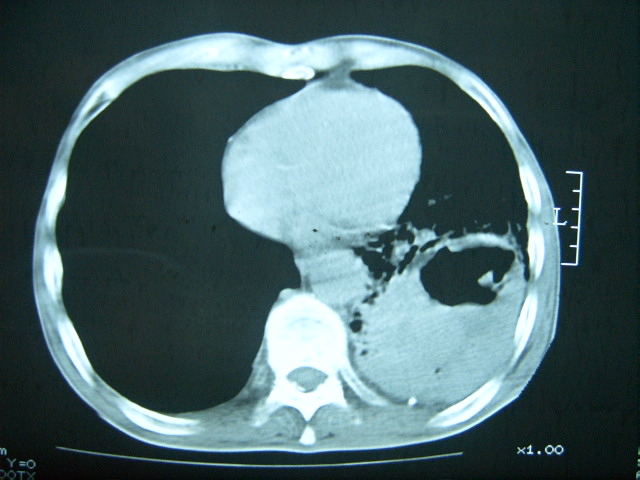

男74岁,咳嗽,寒战,低烧。有糖尿病史。

考虑:1、左下肺脓肿;

2、双肺结核。

糖尿病并发肺脓肿建议治疗后复查

考虑:糖尿病合并:1、左下肺炎继发肺脓肿;

考虑:1、左下肺脓肿;不排除霉菌感染

两肺慢性炎症伴脓肿形成,不除外继发霉菌感染。

两肺结核,左下肺大片实变,内见空洞性病变,壁不规则,结合糖尿病史,考虑:结核性?霉菌性?建议结合实验室检查或治疗后复查。